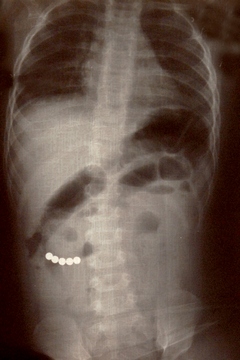

Типичный пример описанной ситуации: здоровый мальчик трех лет был доставлен в отделение неотложной помощи, его мать обеспокоена тем что «он проглотил несколько круглых магнитов». Единственным симптомом, выявленном при осмотре ребенка – была гиперсаливация. На обзорной рентгенограмме брюшной полости врачи увидели, что магниты расположились в эпигастральной области и правом нижнем квадранте живота. Было выполнено эндоскопическое исследование проксимального отдела тощей кишки, в надежде найти там магнит, однако за время подготовки ребенка к процедуре – магнит сместился за пределы досягаемости эндоскопа. Ребенок отпущен домой, маме даны рекомендации осматривать каловые массы ребенка, искать и считать магниты, пока не выйдут все. Кроме того, ребенку был назначен курс слабительного.

За два дня, несмотря на диарею от слабительного, в стуле не было найдено ни одного магнита. Кроме того, у ребенка появилась лихорадка, тахикардия и боль в животе. Повторная рентгенограмма показала, что магниты соединились в правом нижнем квадранте брюшной полости. При лапароскопии выяснилось, что 3 неодимовых магнита, «приклеившись» друг к другу, вызвали перфорацию двух петель подвздошной кишки. Магниты были удалены, перфорации ушиты.